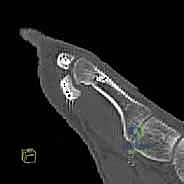

most accurate evaluation, as spasticity is eliminated. Such an examination is always performed at the time of surgery to finalize the treatment plan, as a full passive range of motion is a prerequisite for a tendon transfer.For patients with an equinovarus deformity, the examination focuses on the degree of passive eversion and dorsiflexion. Equinus contracture is often limited to the gastrocnemius muscle but may also involve the soleus muscle.The Silfverskiöld test evaluates the contribution of each component of the gastrocsoleus complex to an equinus contracture, and the amount (in degrees) of passive dorsiflexion is quantified with the knee both flexed and extended. The degree of passive dorsiflexion with the knee extended indicates the absolute magnitude of contracture from the gastrocnemius and soleus. Flexion of the knee relaxes the gastrocnemiusmuscle and allows the contribution of the soleus to be quantified.Selectivity of motor control is commonly impaired in children with cerebral palsy and is tested by asking the patient to contract an isolated muscle group against resistance. This is graded as normal if the patient can isolate the individual muscle and no “overflow” movement is observed in other muscle groups of the same limb. Most commonly, movements of more than one muscle group, or the entire limb, are elicited when testing individual muscle groups. ## IMAGING AND OTHER DIAGNOSTIC STUDIES Although imaging studies are not routinely obtained, plain radiographs of the foot may be helpful in the presence of a fixed deformity.Weight-bearing anteroposterior (AP) and lateral views are reviewed, and a Harris heel view may be considered to evaluate the degree of hindfoot varus in the weight-bearing position.Instrumented motion analysis (gait analysis) is used in many centers to assist with surgical decision making.Slow-motion video is an important component of the assessment and supplements the findings on observational gait analysis.Dynamic electromyelography (EMG) monitors the electrical activity of the tibialis posterior and tibialis anterior throughout the gait cycle, determining whether individual muscles act out of phase or whether they arecontinuously active throughout the gait cycle. 13 Although a surface electrode may be used to assess the tibialis anterior, monitoring of the tibialis posterior requires insertion of a fine needle electrode.One study determined that the deformity was due to the tibialis posterior in 33%, the tibialis anterior in 34%, or both (31%). 9Findings on pedobarography include increased pressure across the lateral midfoot, decreased pressure on the heel at the time of initial contact, and increased pressure on the lateral border of the foot throughout stance phase. ## NONOPERATIVE MANAGEMENT Specific aspects within a comprehensive physical therapy program include stretching exercises to maintain or improve range of motion and strengthening exercises to reduce dynamic muscle imbalance.An ankle-foot orthosis is often required to maintain alignment of the ankle and hindfoot during ambulation.The orthotic facilitates clearance during swing phase by maintaining the foot in a neutral position, prepositions the foot for initial contact with the ground, and promotes stability during stance phase.Night splinting may help to prevent myostatic contracture.Injection of botulinum toxin A (Botox or Dysport) into the tibialis posterior, the gastrocsoleus, or both results in a reversible chemical denervation that decreases spasticity for about 3 to 6 months.In addition to reducing dynamic muscle imbalance, a temporary reduction in spasticity may facilitate stretching exercises, improve bracing tolerance, and delay the need for surgical intervention. ## SURGICAL MANAGEMENT Surgical treatment of the spastic equinovarus foot is offered when the deformity impairs ambulation, interferes with bracing, or both.The goal of tendon transfer is to balance the muscle forces across the hindfoot to maintain a neutral positionduring the swing and stance phases of gait. A split tendon transfer is preferred as transfer of the entire tendon is associated with a significant risk of overcorrection.A normal passive range of motion is a prerequisite. In the presence of fixed soft tissue or bony deformity, concomitant muscle lengthening, with or without osteotomy, may be required to restore motion and alignment.Although an instrumented motion analysis with dynamic EMG will enable the treating surgeon to identify whether the tibialis posterior, the tibialis anterior, or both is/are contributing to the deformity, this technology is not always available. The clinical indications suggested for split tibialis posterior tendon surgery include hindfoot varus during both the stance and swing phases of gait. In contrast, overactivity of the tibialis anterior typically produces varus/supination of the midfoot/forefoot during swing phase.It has been suggested that the procedure be delayed until at least 4 to 6 years of age, and one recent report suggested that consideration should be given to delaying split tendon transfer beyond the age of 8 years ifpossible as there may be a greater risk of recurrence. 2Lengthening of the tibialis posterior muscle may be considered in milder deformities, especially in young patients. Techniques include a distal Z-lengthening or a proximal intramuscular recession. Recognize that it may be very difficult to perform a split tendon transfer if a Z-lengthening has been performed previously.Several techniques have been described for split tibialis posterior transfer.The most common involves transferring the split tendon (posterior to the tibia and fibula) to the peroneus brevis, either at its insertion or just behind the lateral malleolus. This approach focuses on balancing inversion-eversion but does not address dorsiflexion weakness ( FIG 1).An alternate technique, which may be considered when there is inadequate active dorsiflexion, involves anterior transfer of the split tendon through the interosseous membrane to the peroneus brevis ( FIG 2A,B) or the lateral cuneiform (FIG 2C).